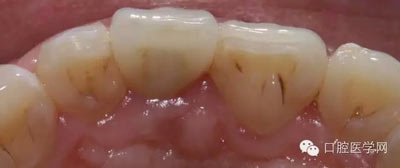

術(shù)前照

檢查:21金屬烤瓷冠修復(fù),顏色及形態(tài)與鄰牙不協(xié)調(diào),牙齦有輕微發(fā)黑,扣痛(-)、松動度(-);11近中鄰面齲壞